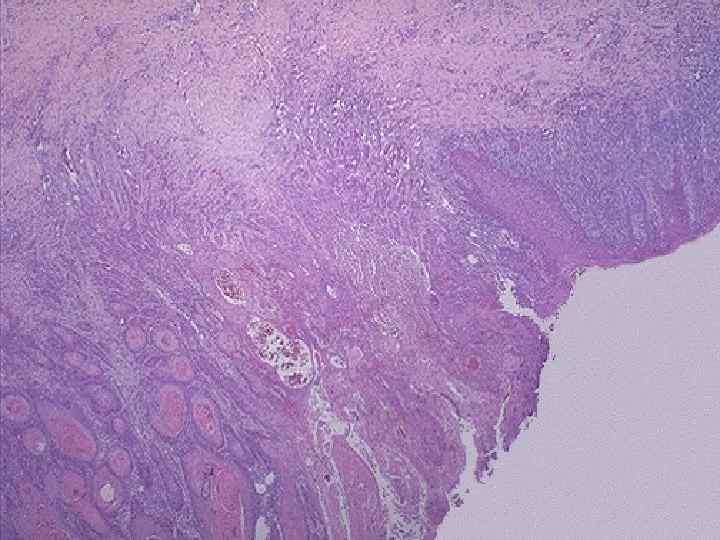

Рак цервикального канала n Рост – эндофитный n Гистологически аденокарциномы